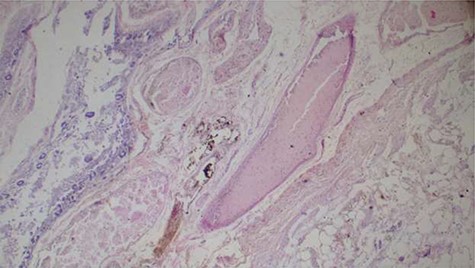

Histopathology analysis of the lung specimens revealed mixed chronic inflammatory infiltrates associated with pulmonary vascular thrombosis and areas of extensive necrosis (Figs 3 and 4). Bowel tissue sections revealed severe ischemic necrosis and mesenteric vessel thrombosis (Fig. 5). Thus, the primary causes of death were ruled to be ischemic colitis and pulmonary thrombosis due to COVID-19. The underlying disease conditions contributing to the cause of death being hypertensive heart disease, diabetes mellitus and septicemia.

Histopathology of lung tissue showing mixed chronic inflammatory infiltrates and vascular thrombosis (hematoxylin and eosin ×100).